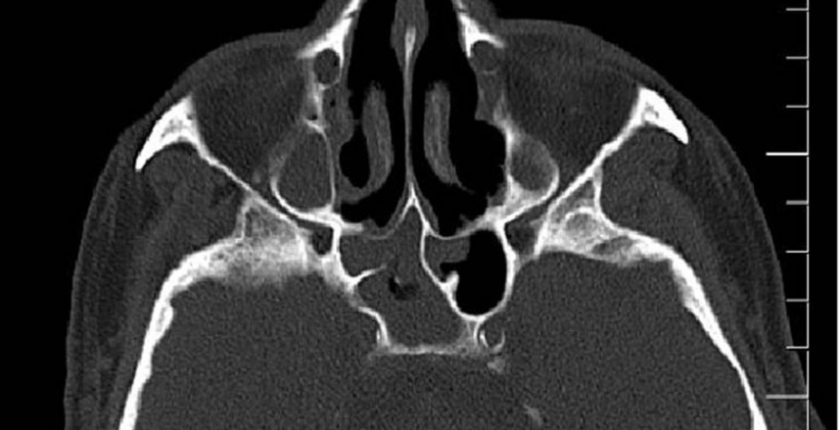

Sfenoid kemik, kafatasının içinde yer alan ve beynin alt kısmında bulunan, karmaşık bir yapıya sahip olan bir kemiktir. “Sfenoid” kelimesi, Yunanca “wedge” yani “maşa” anlamına gelen kelimeden türetilmiştir çünkü şekli, bir maşa veya kama gibi görünür. Bu kemik, kafatasının tabanında, göz çukurlarının hemen gerisinde yer alır ve beyinle doğrudan ilişkili bir dizi önemli yapıyı destekler. Sfenoid kemik, başın ön kısmı, yanları ve arka kısmı arasında köprü görevi görür ve oldukça önemli bir anatomik yapı olarak kabul edilir.

Sfenoid Kemiğin Anatomik Yapısı ve Özellikleri

Sfenoid kemiği, kafatasının orta kısmında yer alır ve beyin, gözler, burun ve ağız gibi önemli organlar arasında bir bağlantı sağlar. Bu kemik, birbirine bağlı bir dizi farklı bölümden oluşur:

Sfenoid Sinüs Enfeksiyonu: Sfenoid kemiğin iç kısmında, sinüsler bulunur ve bu sinüslerde enfeksiyon meydana gelebilir. Sinüzit, burun tıkanıklığı ve baş ağrısı gibi belirtilerle kendini gösterebilir.

Radyolojik Testler: SFenoid kemik problemleri genellikle MRI (manyetik rezonans görüntüleme) ve CT taramaları gibi görüntüleme yöntemleriyle tespit edilir. Bu testler, sfenoid kemiğinin iç yapısını ve sinüsleri değerlendirmeye yardımcı olur.